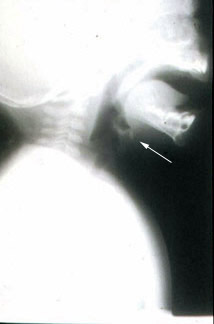

Lateral neck film illustrates normal epiglottis in profile.